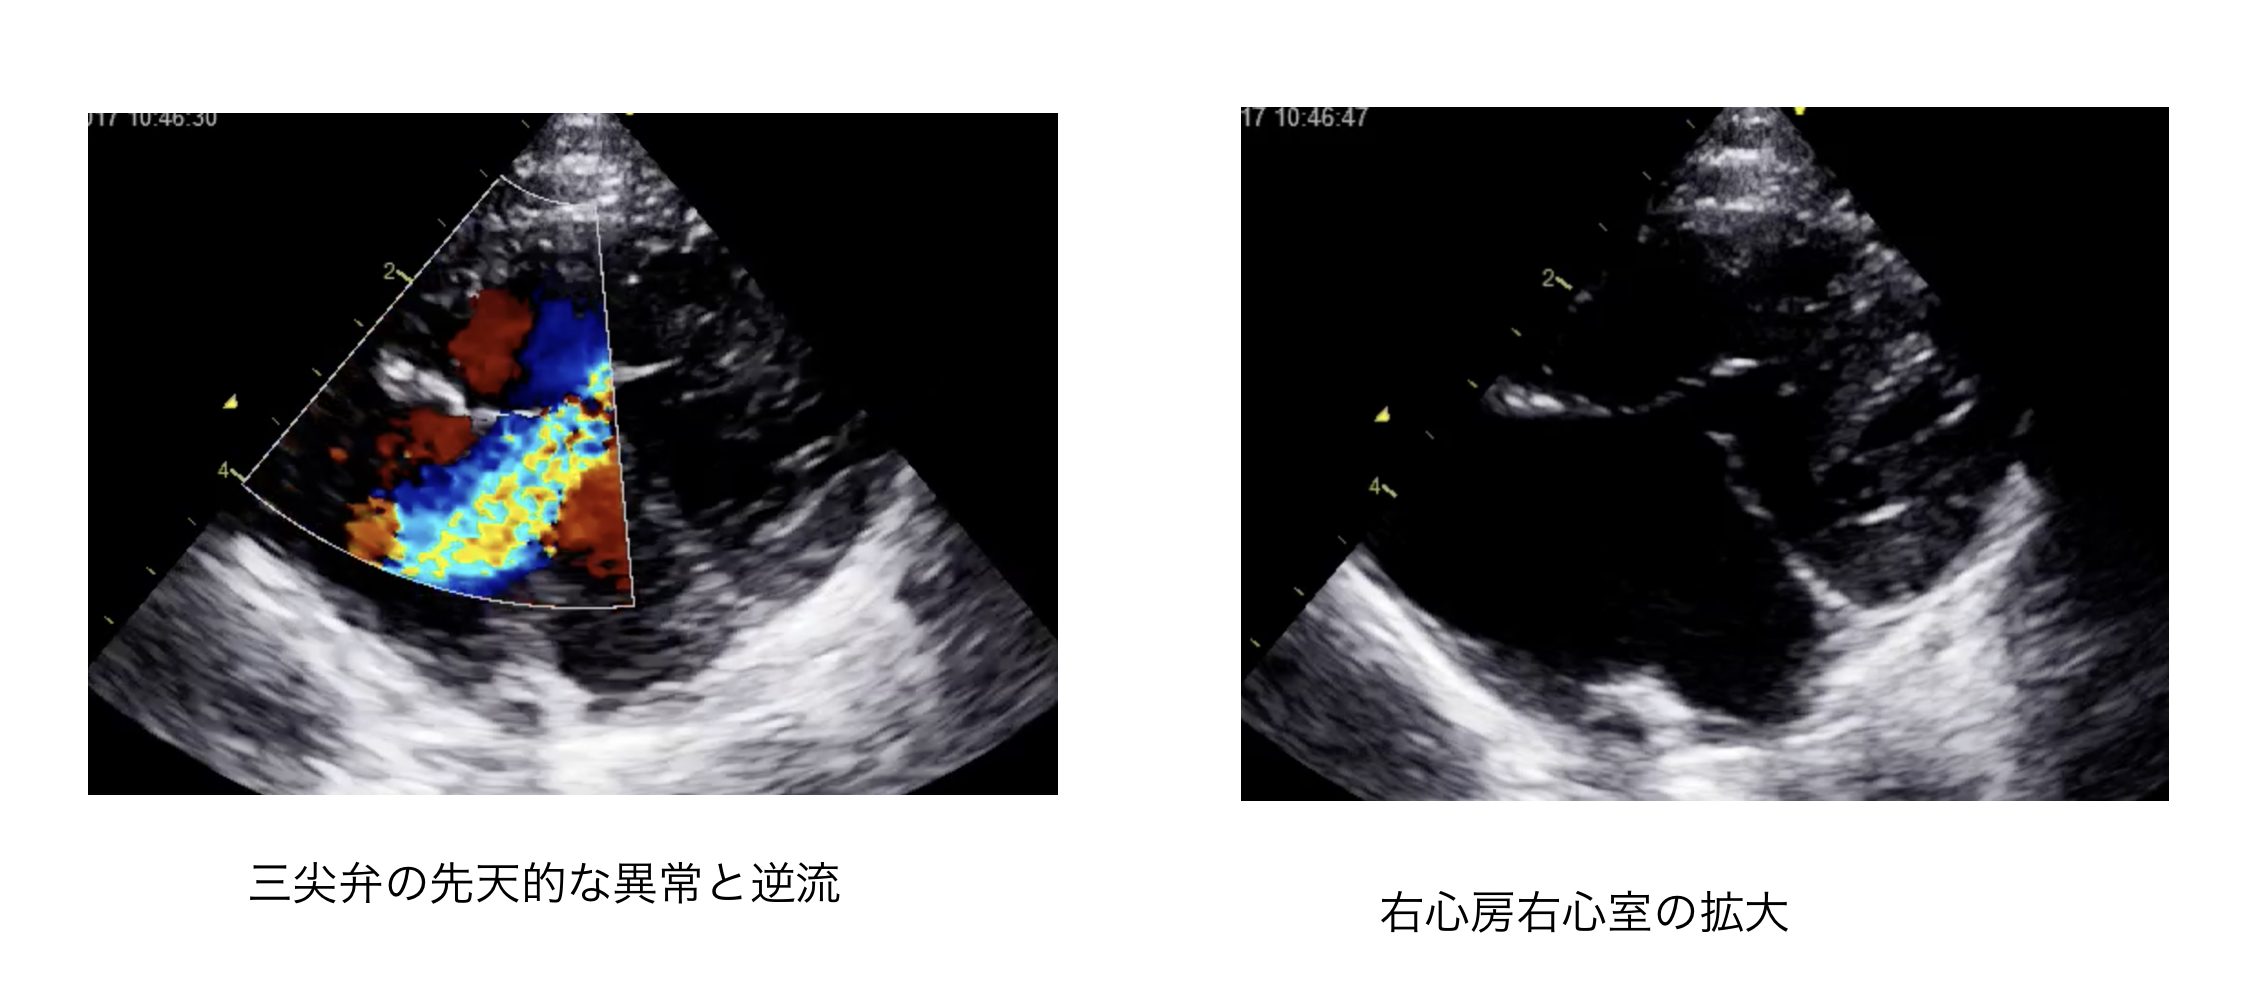

心臓の弁に生まれつき異常がある病気や、心臓の壁に穴が空いている病気、心臓の出口が狭くなってしまう病気など、たくさんの病気が存在します。

(画像は心臓の弁に生まれつき異常がある子猫ちゃんです)